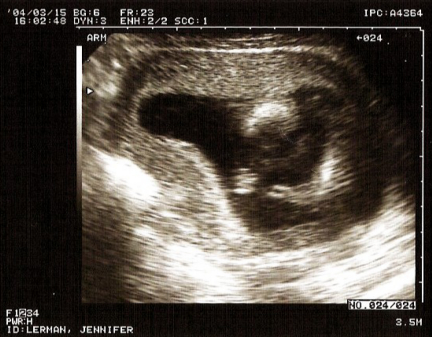

The Newest "Lerman"

The baby is due on August 24th

the body and head

baby's arm and hand